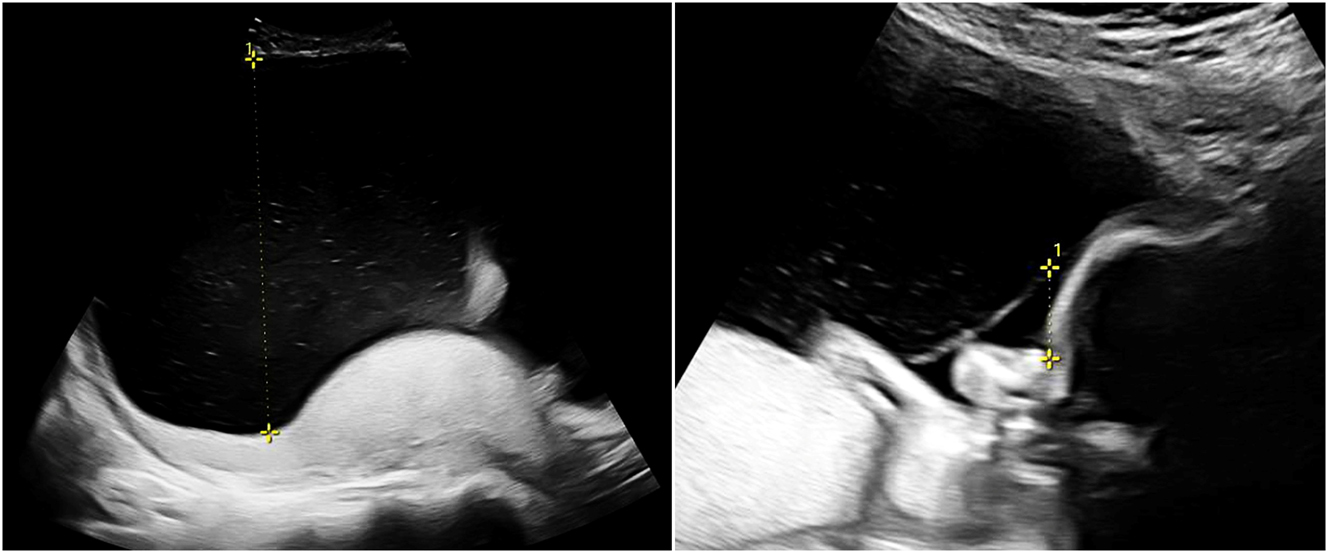

Twin-to-twin transfusion syndrome (TTTS) affects about 10 % of MCDA twin pregnancies and typically manifests between the 16th and 26th week of gestation [2]. It is sonographically defined by oligohydramnios in the donor and polyhydramnios in the recipient, with different cut-offs depending on gestational age. If the deepest vertical amniotic fluid pocket before 20 weeks of gestation meets the criteria of >8 cm in the recipient and <2 cm in the donor, this is referred to as Quintero stage 1 (Figure 2). After 20 weeks the threshold of >10 cm is used for polyhydramnios in the recipient [13], 14]. If such amniotic fluid discordance is accompanied by the absence of bladder filling in the donor, this is referred to as Quintero stage 2. Doppler sonography should be used to assess the hemodynamic stress on both fetuses and is also applied for staging according to Quintero. Typically, the recipient’s cardiac volume overload is reflected in abnormal flow patterns (absent or reversed flow in the a-wave) in the ductus venosus (Figure 3) or pulsatile flow in the umbilical vein, while the donor may present with absent or reversed end-diastolic flow in the umbilical artery. As soon as such signs of hemodynamic compromise occur, this is referred to as Quintero stage 3, although the stage progression does not necessarily have to occur in chronological order [13], 15]. If hemodynamic compromise progresses this can lead to fetal hydrops (Quintero Stage 4, Figure 3) or death (Quintero Stage 5). While the inclusion of further cardiovascular parameters can stratify additional characteristics of fetal pathophysiological changes, this does not improve the prediction of outcome after intrauterine interventions. Despite certain limitations [16], the Quintero stages remain the most practicable classification for TTTS [12], 13].

Sonographic image of a recipient (22 + 0 weeks, same as in Figure 2) with TTTS stage IV with abnormal ductus venosus flow (left) and skin edema (right).